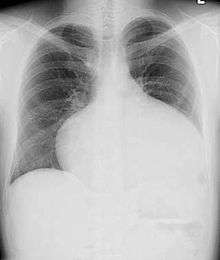

Most individuals with a significant ASD are diagnosed in utero or in early childhood with the use of ultrasonography or auscultation of the heart sounds during physical examination.

Adults with an uncorrected ASD present with symptoms of dyspnea on exertion (shortness of breath with minimal exercise), congestive heart failure, or cerebrovascular accident (stroke). They may be noted on routine testing to have an abnormal chest X-ray or an abnormal ECG and may have atrial fibrillation. If the ASD causes a left-to-right shunt, the pulmonary vasculature in both lungs may appear dilated on chest X-ray, due to the increase in pulmonary blood flow.[40]

Echocardiography

In transthoracic echocardiography, an atrial septal defect may be seen on color flow imaging as a jet of blood from the left atrium to the right atrium.

If agitated saline is injected into a peripheral vein during echocardiography, small air bubbles can be seen on echocardiographic imaging. Bubbles traveling across an ASD may be seen either at rest or during a cough. (Bubbles only flow from right atrium to left atrium if the right atrial pressure is greater than left atrial). Because better visualization of the atria is achieved with transesophageal echocardiography, this test may be performed in individuals with a suspected ASD which is not visualized on transthoracic imaging. Newer techniques to visualize these defects involve intracardiac imaging with special catheters typically placed in the venous system and advanced to the level of the heart. This type of imaging is becoming more common and involves only mild sedation for the patient typically.

If the individual has adequate echocardiographic windows, use of the echocardiogram to measure the cardiac output of the left ventricle and the right ventricle independently is possible. In this way, the shunt fraction can be estimated using echocardiography.